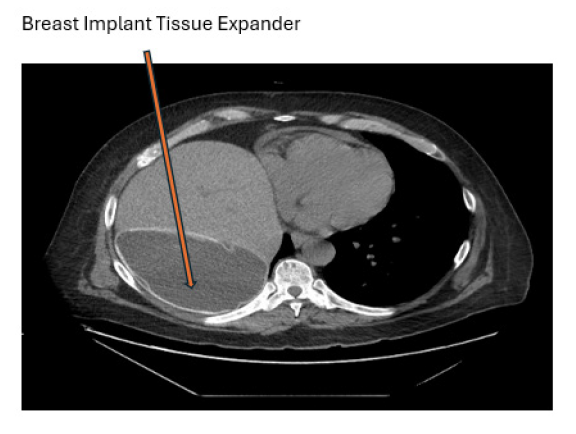

Liver transplantation is commonly used as a treatment for patients with end-stage liver disease due to the improvements in surgical technique, anesthesia, immunosuppression, and imaging [1]. Post-operative complications that could lead to graft failure are categorized into vascular, biliary, parenchymal, and malignant [2]. Malposition of the liver due to incorrect graft size can cause torsion of the venous anastomosis and lead to HVOO [3]. The incidence of HVOO after a standard or cava replacement liver transplant is <2%, but increases to 3-4% after a piggyback technique, and 5-13% when using a partial graft [2]. Although this complication is rare, surgical approach for revision of the anastomosis poses a significant risk for allograft lost and poor patient outcome [2]. Furthermore, literature in stent placement after an HVOO is limited. Several cases in the literature describe the use of bio-inert objects, such as breast implants or abdominal pads to improve anatomical mismatch, as they do not need to be removed [4]. This case describes the incorporation of a breast implant tissue expander to improve positioning and prevent kinking of the allograft (Figures 1-3).

It was noticed that the patient has had right diaphragm eventration due to right phrenic palsy, figure 3. when position the allograft back into the right sub diaphragm, it made the allograft to rotate posteriorly and developed HVOO. The decision was made then to place 850cc breast implant tissue expander posterior to the allograft to allow the outflow to remain widely patent, and the allograft remains in normal position. Figure 1,2,3. Post operatively the patient progressed extremely well, and after a short stay in acute care rehab, he was able to discharge home.

The liver receives 25% of the total cardiac output through the portal vein and hepatic artery. Blood is then drained from the acini via the central veins eventually into the hepatic veins, inferior vena cava, and right atrium. Blockage of blood flow from the liver can result in liver failure. HVOO is a serious complication to liver transplants that could affect the viability of the graft and put the patient in danger. It is divided into three categories based off the location of obstruction – at the level of sinusoids and terminal venules, Budd- Chiari syndrome, and venous obstruction [5]. Kinking of anastomosis due to differences in size between the graft and donor can result in HVOO. In this patient, it led to acute HVOO. The incorporation of bio-inert objects in addition surgical revision of the supra hepatic vena cava anastomosis is increasingly popular. In the context of this case, a breast implant tissue expander was placed posterior to the allograft to prevent kinking due to the patient known history of right phrenic palsy and eventration of the right diaphragm. Other options noticed in the literature include mesh, abdominal pads, inflatable materials, and surgical gloves.